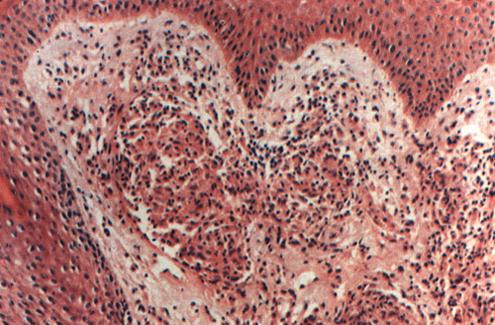

3.BB(中间界线类)由于免疫状态不稳定,此种类型少见,不治疗常降级为LLs,随着治疗通常升级到BT。此类麻风的病理变化为上皮样细胞肉芽肿(少数病例可能有少量的巨噬细胞灶),没有巨细胞,淋巴细胞少,常呈弥散性分布。表皮下带清晰,神经无明显肿胀或正常,神经束膜有层状改变并有上皮样细胞浸润,抗酸杆菌3+~4.5+,细菌分布不均匀,有些区域数量较少(照片4)。

照片4 中间界线类麻风(BB)

真皮水肿,有“无浸润带”及上皮样细胞浸润灶,淋巴细胞少,未构成包围。